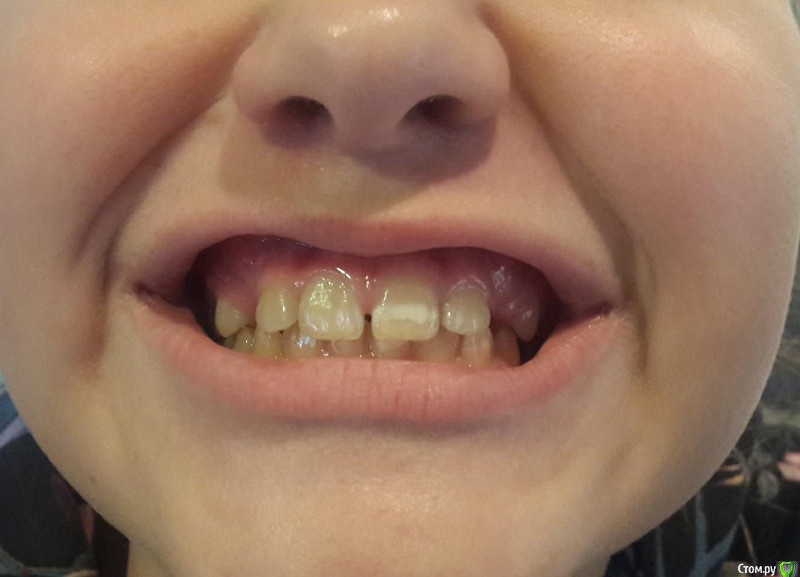

Винкс Опубликовано 22 декабря, 2017 Поделиться Опубликовано 22 декабря, 2017 Ребенок 11 лет, надо ли ждать прорезывания клыков или уже бежать к доктору. Ссылка на комментарий